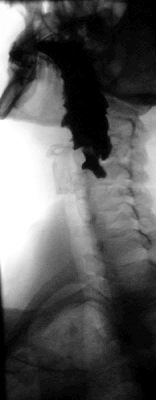

Главным методом в диагностике дивертикулов является полипозиционное рентгенконтрастное исследование, которое позволяет выявить локализацию, форму, размеры дивертикула. В роли контраста используют бариевую смесь. Также обязательно эзофагоскопическое исследование позволяющее выявить изменения слизистой, а также наличие различных осложнений (кровотечение, полип, рак).